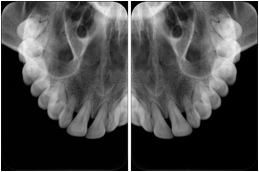

2. A patient requests cosmetic surgery to enhance their facial appearance. The case requires consultation between an orthodontist in New York and an oral surgeon in California. The cephalometric series of 2D projections constructed from the volumetric CT data that is used for the discussion is arranged by a Structured Display for transfer between the two practitioners.

Cephalometric Series Structured Display

Figure OO-2. Cephalometric Series Structured Display